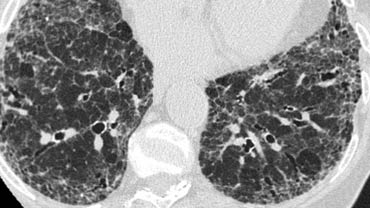

Bệnh nhân này nhập viện với triệu chứng khó thở cấp tính và phim X-quang ngực bình thường (không trình bày).

HRCT lúc nhập viện (trái) cho thấy các vùng kính mờ theo phân bố tiểu thùy.

HRCT kiểm tra mười ngày sau (phải) cho thấy các tổn thương đã thoái lui hoàn toàn mà không cần điều trị.

Các tổn thương được cho là do viêm phổi quá mẫn.